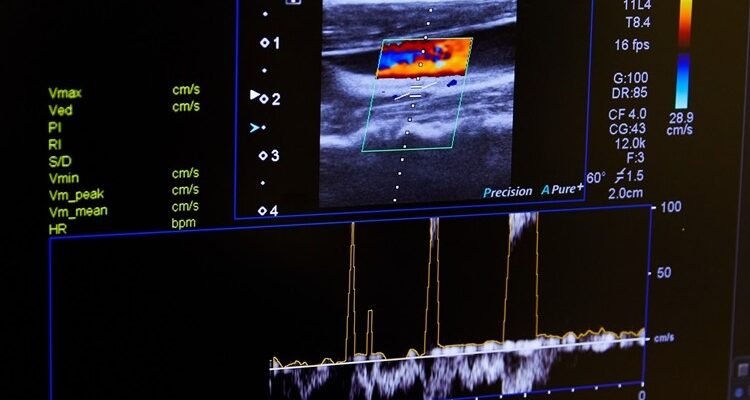

- Медицина: Доплерографія — метод, що використовує ультразвук для вивчення кровотоку. Вона здатна попередити про звуження артерій чи тромби.